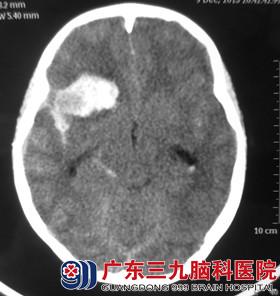

小隐今年13岁,一天凌晨5点左右突发头痛,呈进行性加重,伴有意识障碍,急送当地医院,行头颅CT检查提示蛛网膜下腔出血,右侧额颞叶出血并破入脑室系统,右侧额颞叶脑出血,建议转上级医院行进一步治疗。

经联系转入广东三九脑科医院综合神经外科,查体患者GCS评分8分,行头颅CTA检查提示右侧大脑中M1段巨大囊性动脉瘤。完善相关检查后,由鲁明主任主刀,在全麻下行右侧大脑中动脉瘤夹闭术+右侧额颞顶去骨瓣减压术+左侧脑室外引流术,术中显微镜下在M1起始处见瘤颈,予动脉瘤夹夹闭,载瘤动脉及周围动脉分支保护完好,手术顺利结束,术后经过治疗护理,小隐未出现功能障碍,康复出院。

术前CTA 术前CT